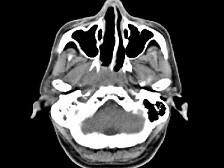

男,52岁,血涕3月余。CT如图所示,最可能的诊断为 ( )A、小唾液腺瘤B、咽旁脓肿C、咽旁混合瘤D、咽部神经纤维瘤E、鼻咽癌

问题 男,52岁,血涕3月余。CT如图所示,最可能的诊断为 ( )

选项 A、小唾液腺瘤 B、咽旁脓肿 C、咽旁混合瘤 D、咽部神经纤维瘤 E、鼻咽癌

答案 E